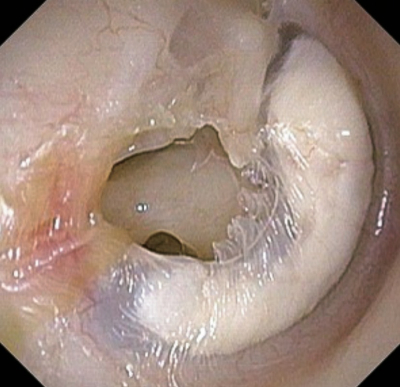

慢性化膿性中耳炎の手術を目的に来院した患者の右耳の鼓膜写真を別に示す。視認されないのはどれか。

a. ツチ骨

b. アブミ骨

c. 鼓膜穿孔

d. 耳管開口部

e. 鼓膜石灰化